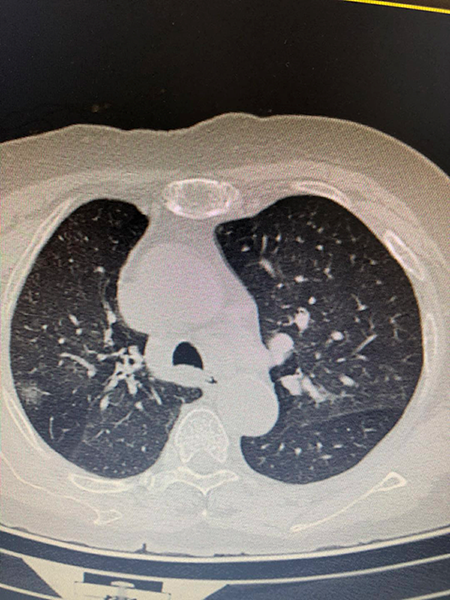

海宁的吴女士(化名)因胸闷、咳嗽久不见好转,进行了胸部CT检查,结果在肺部发现了35px的结节,并且不排除肺癌可能。

知道结果的吴女士十分担心,有医生建议先进行手术比较保险,但王剑飞认为应先进一步确诊,不着急手术。后经过一段时间的消炎、雾化吸入、中药调理等治疗,一个月后,吴女士的结节缩小至6mm,一切症状都显示并没有癌变危险,保持三个月随访即可。这令吴女士安了心,也免除了手术的痛苦。

故事二、肺部磨玻璃结节别纠结

徐先生(化名)被查出肺部磨玻璃结节已有数月,且有三个——最大的约7mm,最小的5mm左右。自此,他陷入了惶惶不安,四处寻医,遍查医典,掌握了十分丰富的与肺部结节相关的医学知识。但他还是无法作出决定——开刀,或不开刀?

后经过王剑飞的一番分析与开导,徐先生终于决定手术,术后诊断——最大的是微浸润癌,其余2个是原位癌。虽然从预后看,开刀早晚差别不大,但徐先生终于安心了,又能轻松面对生活了。而对于王剑飞能想病人所想,细心考虑每一个患者的顾虑,徐先生感到十分暖心及感激。